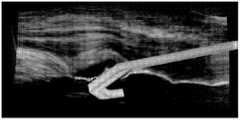

如图10A与图10B所示,图10A与图10B为实施例的假手模型与超声波容积(ultrasound volume)的校正的示意图。实体医学影像三维模型14b及人造医学影像三维模型14c彼此之间有关联,由于假手的模型是由计算机断层影像容积所建构,因此可以直接拿计算机断层影像容积与超声波容积间的位 置关系来将假手和超声波容积建立关联。As shown in FIG. 10A and FIG. 10B, FIG. 10A and FIG. 10B are schematic diagrams of the correction of the artificial hand model and the ultrasound volume of the embodiment. The physical medical

如图10C与图10D所示,图10C为实施例的超声波容积以及碰撞检测的示意图,图10D为实施例的人造超声波影像的示意图。训练系统要能仿真真实的超声波换能器(或探头),从超声波容积产生切面影像片段。不论换能器(或探头)在任何角度,模拟的换能器(或探头)必须描绘对应的影像区段。在实作中,首先检测医疗探具21与超声波体之间的角度,然后,片段面的碰撞检测是依据医疗探具21的宽度及超声波容积,其可用来找到正在描绘的影像区段的对应值,产生的影像如图10D所示。例如人造医学影像数据是立体超声波影像来说,立体超声波影像有对应的超声波容积,模拟的换能器(或探头)要描绘的影像区段的内容可根据立体超声波图像映射的位置产生。As shown in FIGS. 10C and 10D, FIG. 10C is a schematic diagram of ultrasonic volume and collision detection according to an embodiment, and FIG. 10D is a schematic diagram of an artificial ultrasound image according to an embodiment. The training system must be able to simulate a real ultrasonic transducer (or probe) and generate slice image fragments from the ultrasonic volume. Regardless of the angle of the transducer (or probe), the simulated transducer (or probe) must depict the corresponding image segment. In the implementation, the angle between the